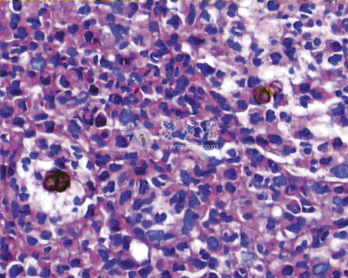

着色芽生菌病

着色芽生菌病,又称着色霉菌病,是一种慢性、局限性皮肤和皮下组织感染,由一组深真菌...